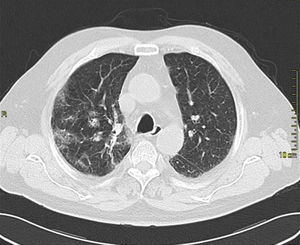

Case presentationIn October 2010 a 74-year-old Caucasian male was admitted because of fever, anuria and mialgia lasting for 2 days. He had no history of renal disease and reported previous normal values of renal function. A month earlier he had travelled to a region of Southern Italy. Physical examination showed normal blood pressure, dyspnoea and jaundice without other dermatological findings; the patient was anuric with 2+pedal oedema. Initial laboratory work-up indicated a total leucocyte (WBC) count of 11,300/μL (neutrophils 88.3%, lymphocytes 11%, eosinophils 0.7%), a haemoglobin level of 9.7g/dL, platelets count of 13,000/μL, serum creatinine 5.25mg/dL, blood urea nitrogen (BUN) 67g/dL, total protein 6.7g/dL, albumin 2.9g/dL, serum sodium 130mEq/L, serum potassium 3.3mEq/L, serum calcium 8.4mg/dL; total cholesterol 254mg/dL; LDL cholesterol 48mg/dL; HDL cholesterol 22mg/dL, procalcitonin 45.71ng/mL, normal value (n.v.)<0.09, Reactive C Protein 22.70mg/dL, n.v.<0.30, ferritin 1300μg/L. Complement C3 and C4, Immunoglobulin G, A and M, kappa and lambda light chains, clotting profile, AST and ALT levels were in the normal range. Total and direct bilirubin values were respectively 4.3 and 2.1mg/dL. Immunological (anti-neutrophil cytoplasm antibodies, anti-nuclear antibodies, anti-double stranded DNA antibodies, anti-extractable nuclear antigen antibodies, anti-phospholipids antibodies, rheumatoid factor) tests were unremarkable. A chest X-ray showed multiple bilateral ground-glass opacities (Fig. 1). A thoracic CT-scan revealed multiple bilateral consolidations and bilateral pleural effusion (Fig. 2). There was to electrocardiogram evidence of normal sinus rhythm and transthoracic echocardiography demonstrated no wall motion abnormality. An abdominal ultrasonography and a CT-scan revealed no abnormalities of liver, gallbladder, kidneys, spleen and pancreas. At the same time of antibiotic, platelet transfusion and diuretic therapy we started continuous venovenous haemofiltration (CVVHF) with weight loss and rapid regression of dyspnoea. Two days after admission the patient showed melena. Subsequent laboratory tests indicated: normal oncologic screening; no signs of haemolytic anaemia; red blood cells and WBC in urinary sediment; a total of 475mg of protein was excreted during a 24-h urine collection; blood cultures examination, tuberculin reaction and HBV, HCV, CMV, EBV, Adenovirus, Chlamydia Pneumoniae and Mycoplasma Pneumoniae screening were negative. During hospitalization we observed a worsening of liver function (total and direct bilirubin respectively 17.30 and 10.50mg/dL, gammaGT 267IU/L, n.v. 7–50, LDH 1027IU/L, n.v. 266–530, AST: 67IU/L, n.v. 10–42, ALT 96IU/L, n.v. 10–45) and inflammation parameters (WBC count 25,250/μL, neutrophils 76.6%, ferritin 4200μg/dL). An abdomen CT-scan highlighted greatly thickened gallbladder and bile duct walls with contrast enhancement, peritoneal effusion and swelling of the visceral adipose tissue (Fig. 3). We performed the Leptospira IgM test (enzyme immunoassay) with positive result. After platelets and erythrocytes transfusions and omeprazole therapy, we started 3g/day ceftazidime and 50mg/day prednisone therapy with a progressive improvement in renal function and general conditions; after 10 days of admission we stopped CVVHF. A thoracic CT scan showed resolution of previously observed lesions. The patient was discharged on day 18. Final laboratory parameters were: creatinine: 0.93mg/dL, BUN: 26mg/dL, total and direct bilirubin respectively 6.50 and 3.40mg/dL, AST: 47IU/L, ALT: 84IU/L, gammaGT: 137IU/L, LDH: 609IU/L, WBC 3420/μL, Hb: 8.3g/dL, and PLT: 262,000/μL.